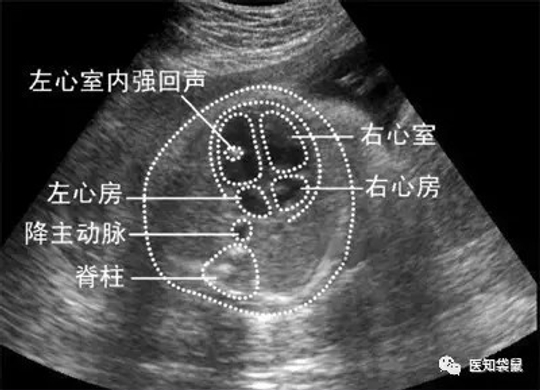

3、心内强回声

心内强回声指在乳头肌或任意心室内出现的回声与骨质强度类似的微小钙化灶,可存在于单一心室或双心室,可单发也可多发,有1.5%~4%的胎儿可出现心内强回声。

有心内强回声不一定说明胎儿心脏有问题,与染色体异常也没有必然联系。研究发现,很多年龄不足35岁的准妈妈在做超声检查时,会发现胎儿心内强回声,但属于正常生理表现,这有可能是乳头肌的镜面发射回声。所以,当怀疑胎儿心内强回声时,医生通常会从多个角度查看来加以判断。

但如果发现胎儿有典型的心内强回声,则需要对胎儿进行细致的超声检查,以明确有无结构异常。如果合并其他明显的结构异常或隐匿症状,医生通常会建议你进行羊膜腔穿刺术,以排除染色体畸形。